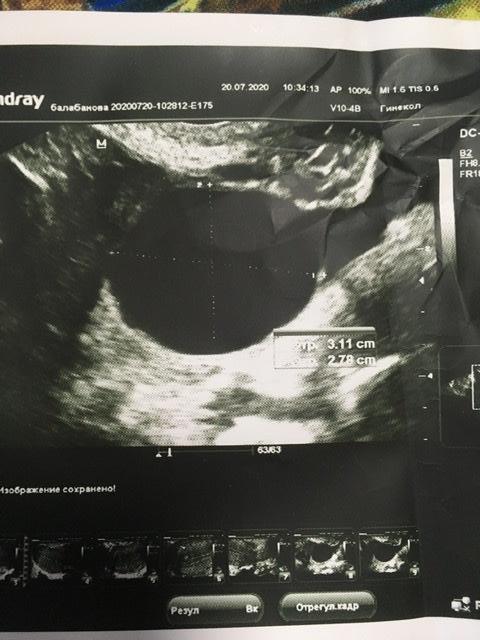

Девочки, у кого были полипы эндометрия , небольшие , у меня 3/4мм .может полип быть без ножки ? или это может быть что-то другое, аномалия эндометрия какая-то . Откликнитесь , у кого какие были , и возможно кто-то знает причину появления полипа в матке .

У меня был , образовался после приема клостилбегита , давно , удалили в 2016 , в прошлом цикле стимулировались без таких препаратов , просто укол овитреля , разве может быть от него? Это же хгч (

Большой полип был? Сколько мм , не помните?

Ну на мм больше чем у меня , а беременели в естественном цикле?